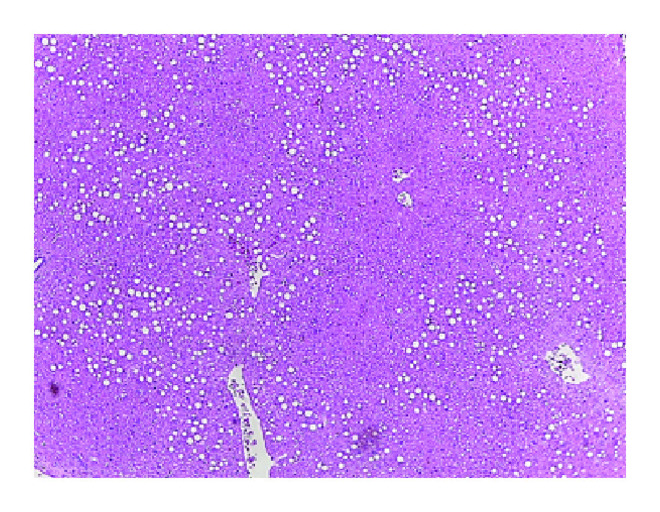

3.2. Improvement of NAFLD in Pioglitazone-Treated CAR−/− Mice

In histologic examination, hepatic steatosis was slightly aggravated in CAR−/− mice (Figure 2(b)) compared with CAR+/+ mice (Figure 2(a)), but was nearly completely abolished after TCPOBOP treatment, which is a strong activator of CAR (Figure 2(c)). After pioglitazone treatment, fat globules remained in the liver of CAR+/+ mice (Figure 2(d)). In contrast, liver steatosis was markedly improved by pioglitazone treatment in CAR−/− mice (Figure 2(e)). However, in TCPOBOP-treated mice, we observed no additional effect of pioglitazone on NAFLD (Figure 2(f)), possibly because the strong effects of TCPOBOP ameliorate fatty liver [16].